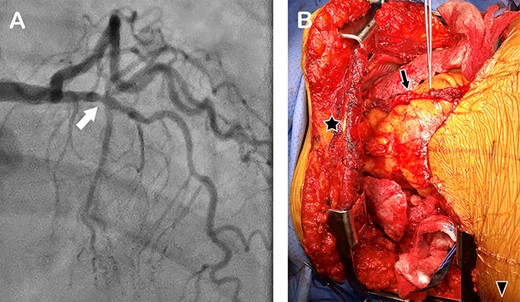

Sketches depicting the harvest of LITA via clamshell incision (A), ligation, division of the RITA and sternum (B), a bone hook was used to lift the lower sternal edge anteriorly and superiorly to expose the distal end of the LITA (C), which was harvested and divided (D), the proximal part of the LITA was harvested by elevating the superior sternal edge with a bone hook (E).

First, right and left anterolateral thoracotomies at the fourth intercostal spaces were performed (Fig. 2A) and the left and right internal thoracic arteries (RITA) were exposed and freed for 2 cm in both directions. We ligated and divided the RITA, then divided the sternum transversely while preserving the LITA (Fig. 2B). Using a bone hook, we lifted the lower edge of the divided sternum superiorly and anteriorly (so as not to put tension on the LITA) to expose the lower part of the LITA (Fig. 2C). We freed the LITA from the chest wall distally and divided it at the bifurcation after administering 3000 units of heparin intravenously (Fig. 3D). By placing two Finochietto retractors in the right and left fourth intercostal spaces, and using a bone hook to elevate the superior edge of the sternum, we were able to expose and harvest the entire upper portion of the LIMA up to its origin (Fig. 2E). The harvested LIMA (Fig. 1A) was covered with papaverine soaked sponge and tucked in the left pleural cavity for later use.